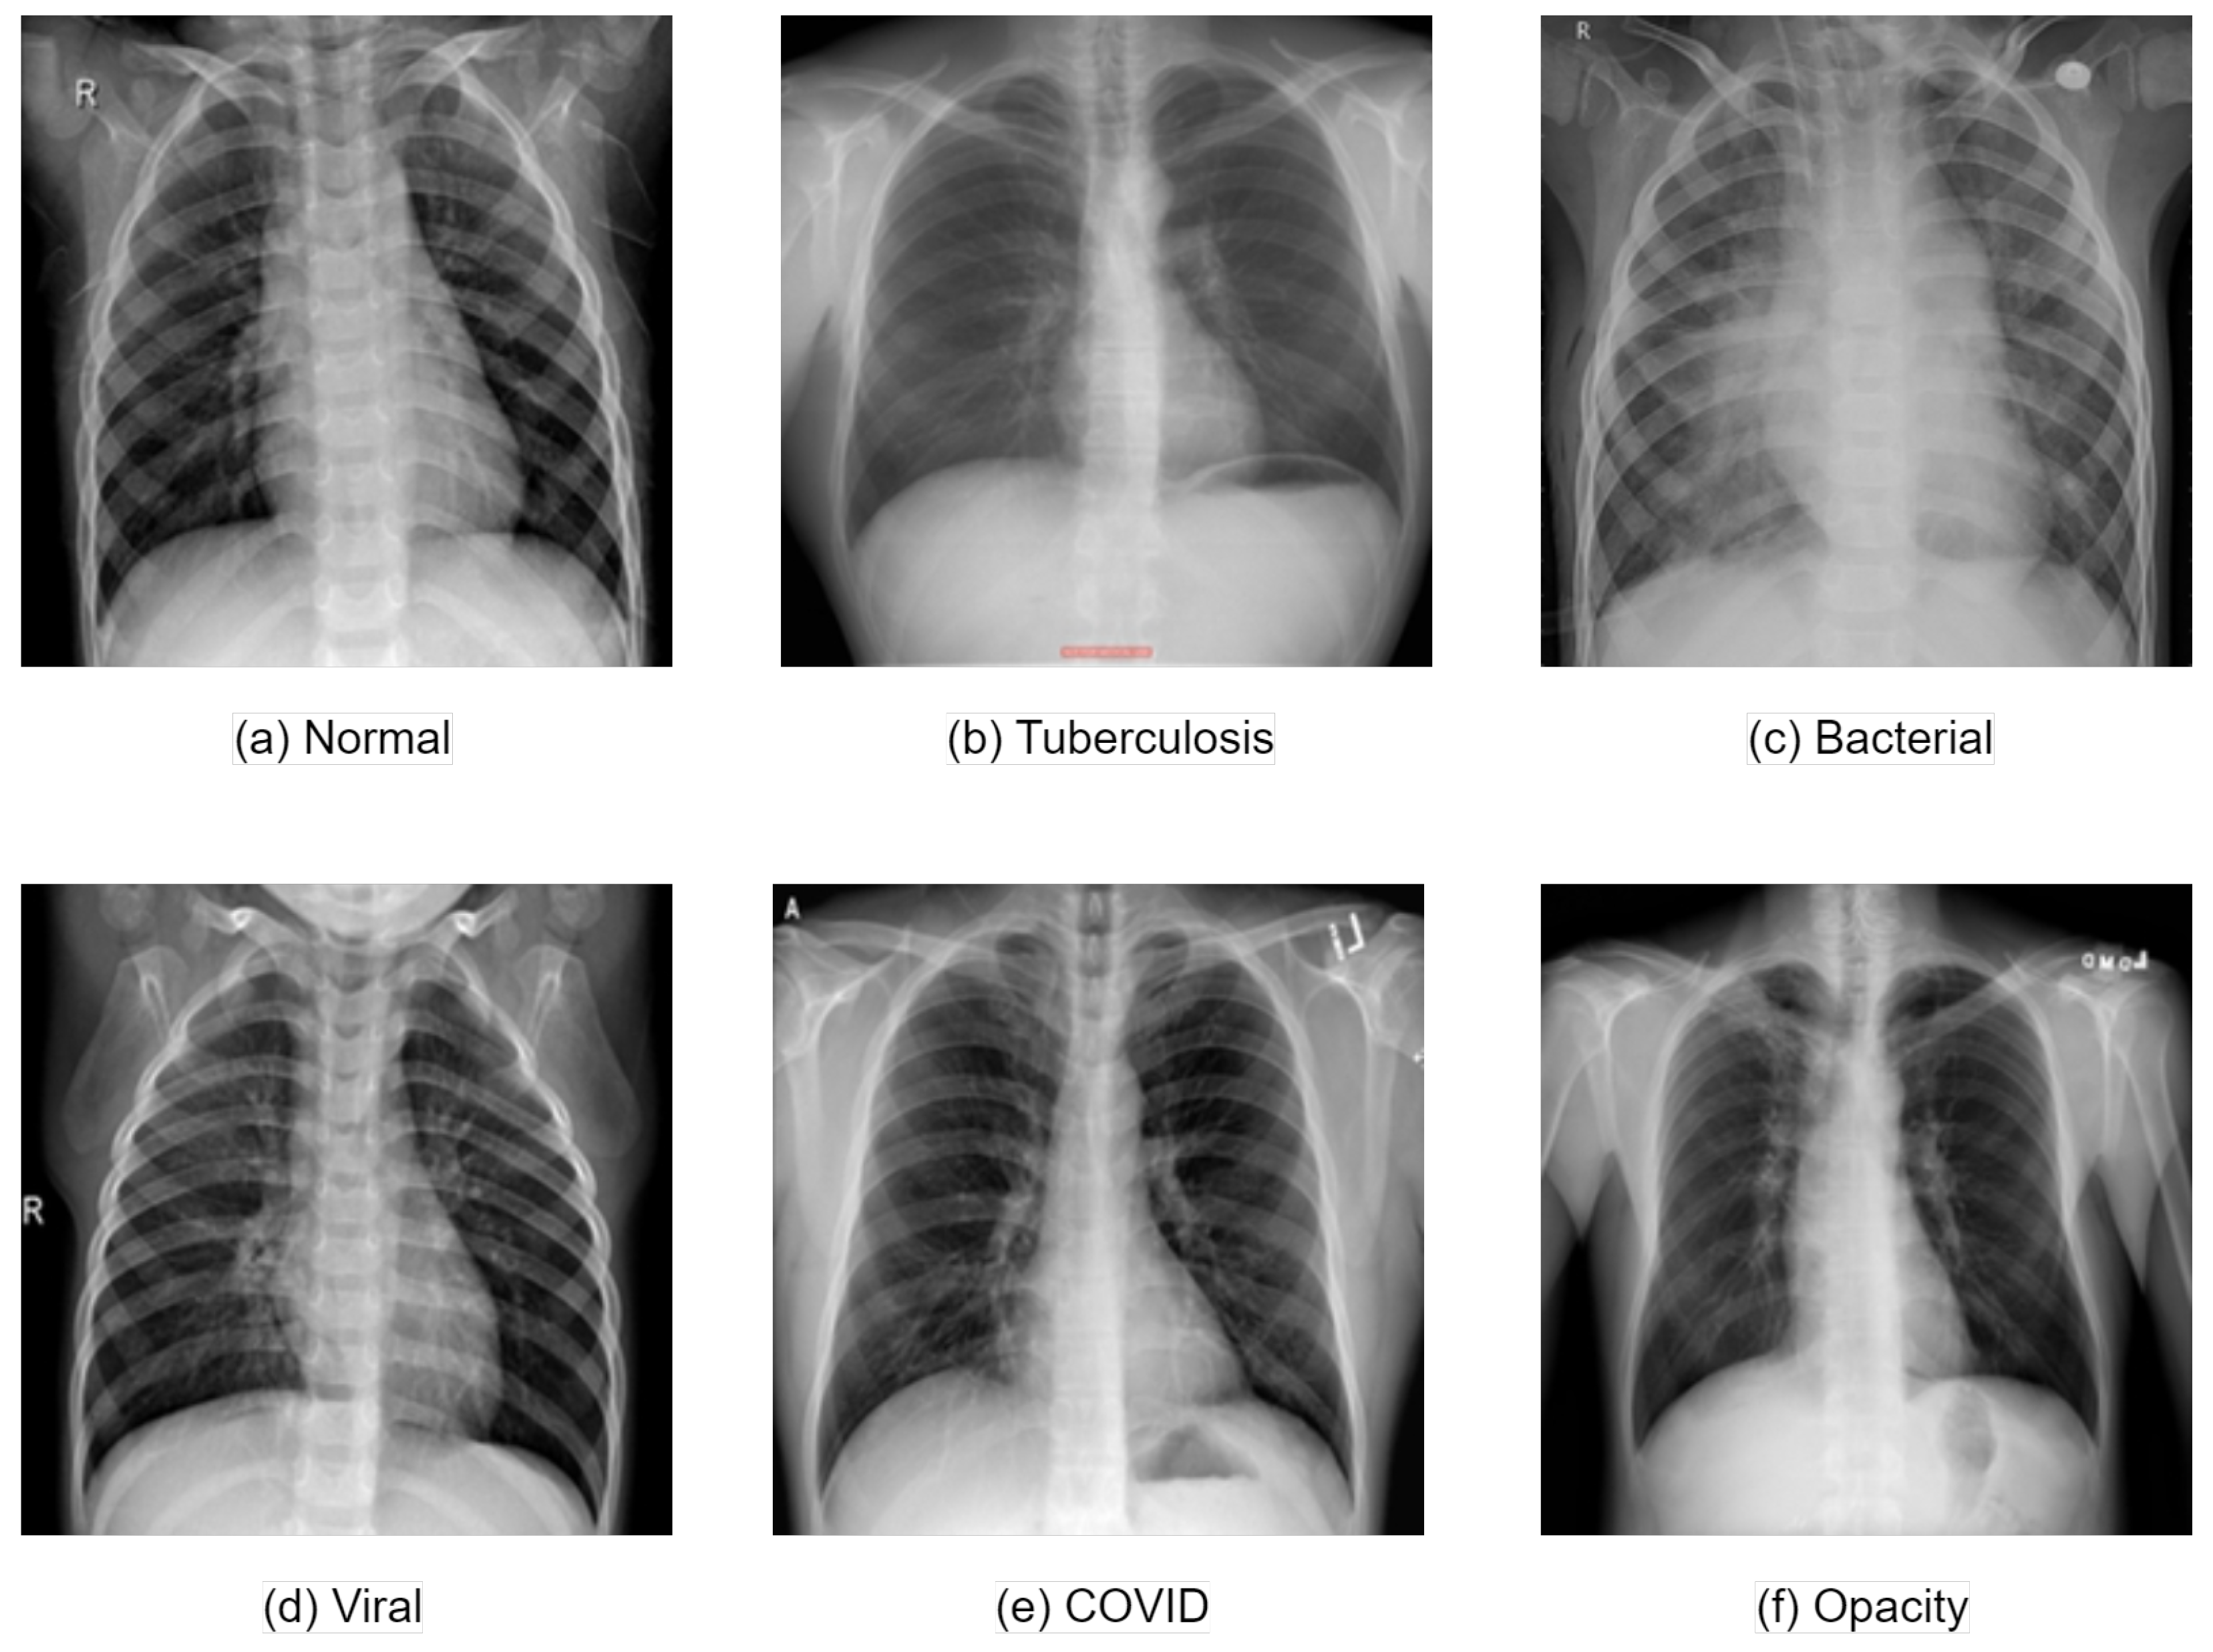

In our research, we concentrated on the identification of multiple categories using three distinct collections of medical data, all of which consisted of chest X-ray images. Our collection comprised a total of 27,445 images that included both normal cases and five different types of lung diseases. The initial collection that we utilized came from [30], which provided a diverse set of images: 3616 COVID-19 positive cases, 10,192 images classified as normal, 6012 showing lung opacity, and 1345 images identified as showing viral pneumonia. The second collection was sourced from [31], which included 3500 images of tuberculosis and another 3500 images of normal chest X-rays. From this collection, we exclusively used the images representing tuberculosis for our analysis. The third collection of images was acquired from [32], which included 2780 images of bacterial pneumonia and 1493 of viral pneumonia. For the purposes of our study, we focused on the images of bacterial pneumonia. Figure 1 illustrates sample chest X-ray images from these collections, showcasing the different categories involved. Additionally, Figure 2 presents the chest X-ray image distribution across the various categories from our collection.

Figure 1.

The samples of chest X-ray images from the collection.